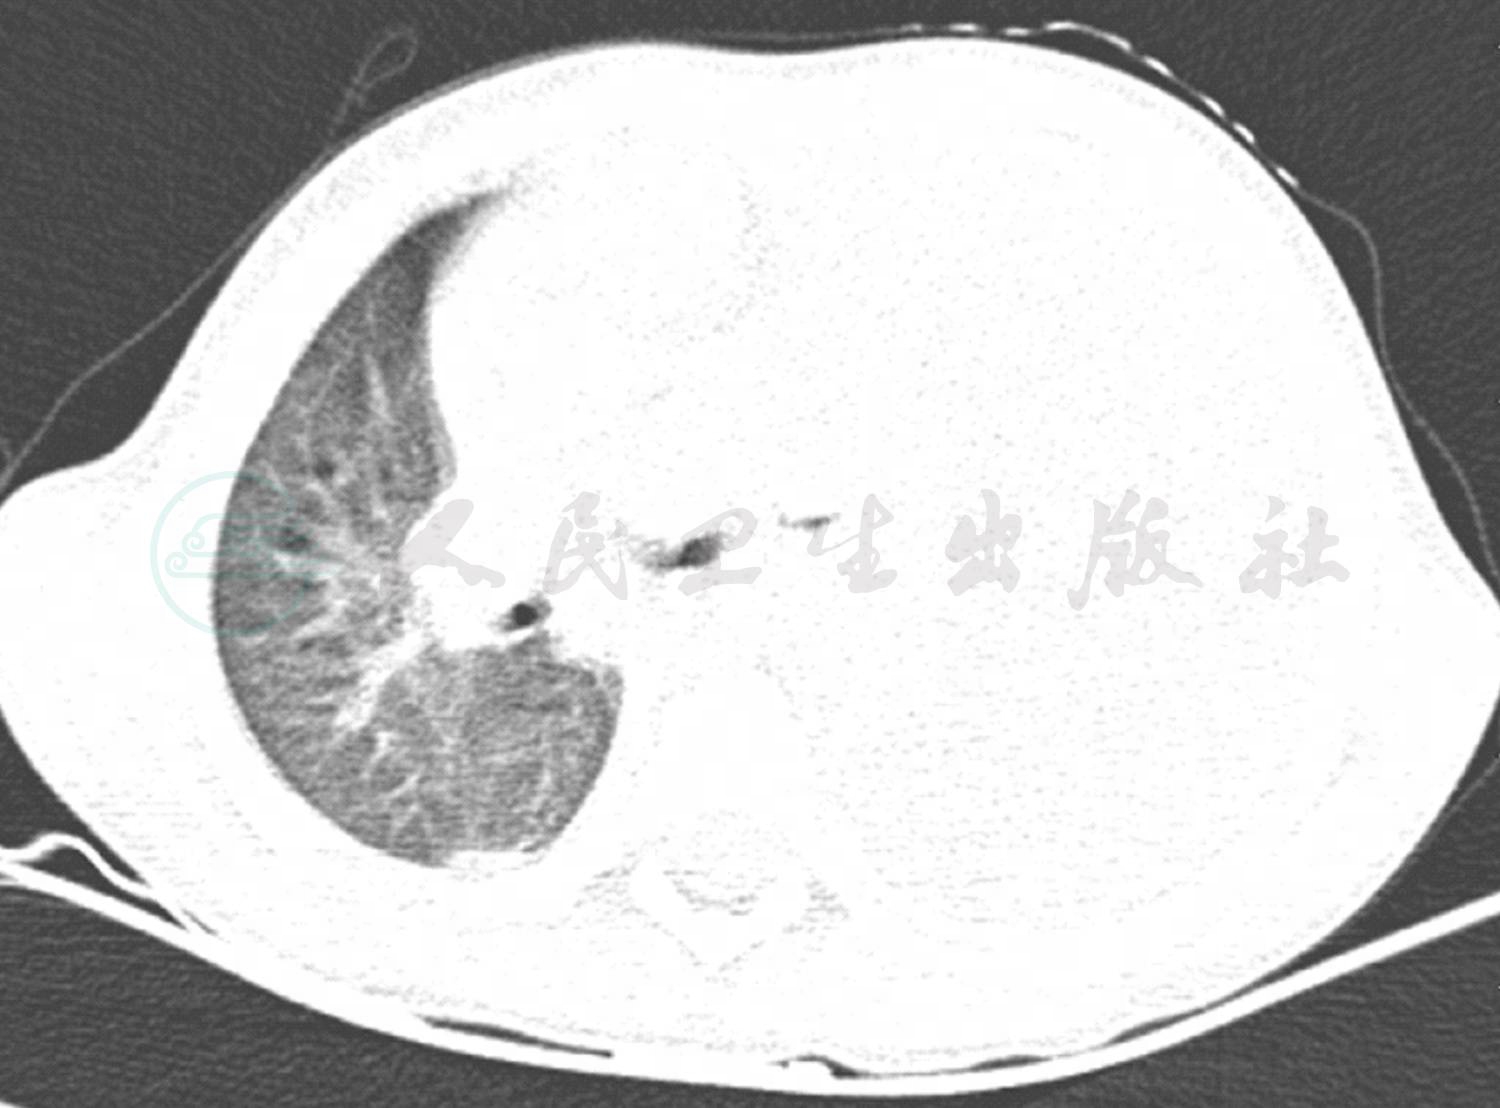

入院后患儿完善彩超定位等各项基础检查后,给予患儿胸腔穿刺术,抽取胸腔积液送化验检查。肺CT回报:左侧胸腔大量积液,伴左肺膨胀不良;右肺散在炎症(图1)。考虑患儿胸腔积液量较大,自行吸收困难,紧急联系外科行胸腔闭式引流。随后在次日胸腔积液的细菌培养中检查到肺炎链球菌生长,药敏结果提示对利奈唑胺敏感,考虑患儿血象高,感染中毒症状明显,该药组织浓度高,穿透性好,随即给予更换该药治疗。于血液检查时发现存在肺炎支原体感染,后给予阿奇霉素联合治疗。另外,患儿血液生化及电解质提示有轻微异常,给予患儿丙种球蛋白、白蛋白等营养支持及维持电解质平衡治疗。经过治疗患儿的体温及感染中毒症状得到了改善,血常规、C反应蛋白等炎症指标均明显下降,但经过10天左右的治疗体温仍有反复,波动在38℃左右。经过病例讨论建议完善纤维支气管镜检查,结果提示支气管内膜损伤较重,有较多分泌物堵塞。结合血液检查中存在肺炎支原体感染,虽然经过大环内酯类药物治疗,仍然不好,可能存在大环内酯类药物耐药,或引发了机体的免疫反应,符合难治性支原体肺炎的诊断,给予患儿静脉滴注甲泼尼龙琥珀酸钠1mg/(kg·次),每天2次,治疗5天,患儿体温逐渐平稳,未再次发热。患儿经过1个多月治疗,体温恢复正常,呼吸平稳,右肺炎症吸收,左肺膨胀及实变好转(图2),出院进行康复治疗。

图1 肺CT平扫示:左侧胸腔大量积液,伴左肺膨胀不良;右肺散在炎症